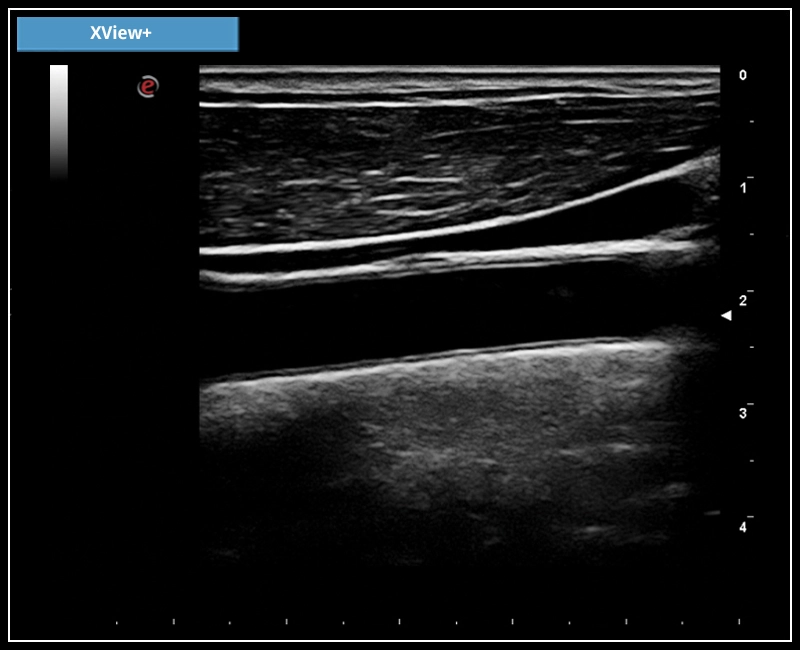

MyLab™X7 - XView+

MyLab™X7 - XView+